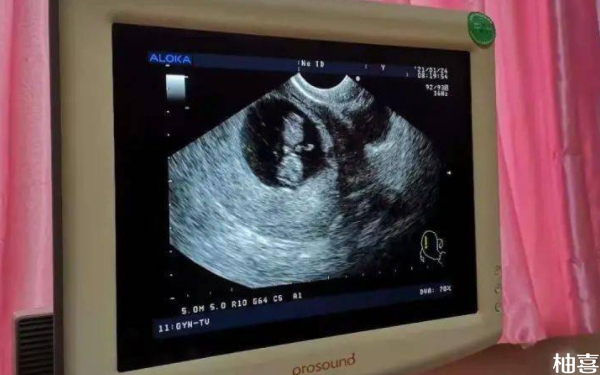

孕期B超臀位朝下一般生男孩几率大吗?

女性在孕期做B超后,如果胎儿臀位朝下的话,其生男孩几率并不能确定。一般来说,臀位是胎儿在母体内的一种胎位,指的是胎儿的臀部朝下,头部朝上,属于异常胎位。另外,臀位的形成主要与孕妇骨盆狭窄、腹壁松弛、多胎、羊水过多、胎儿畸形等因素有关,与胎儿的性别无关。因此,在孕期应关注胎儿健康,及时纠正异常胎位,确保分娩的顺利进行。